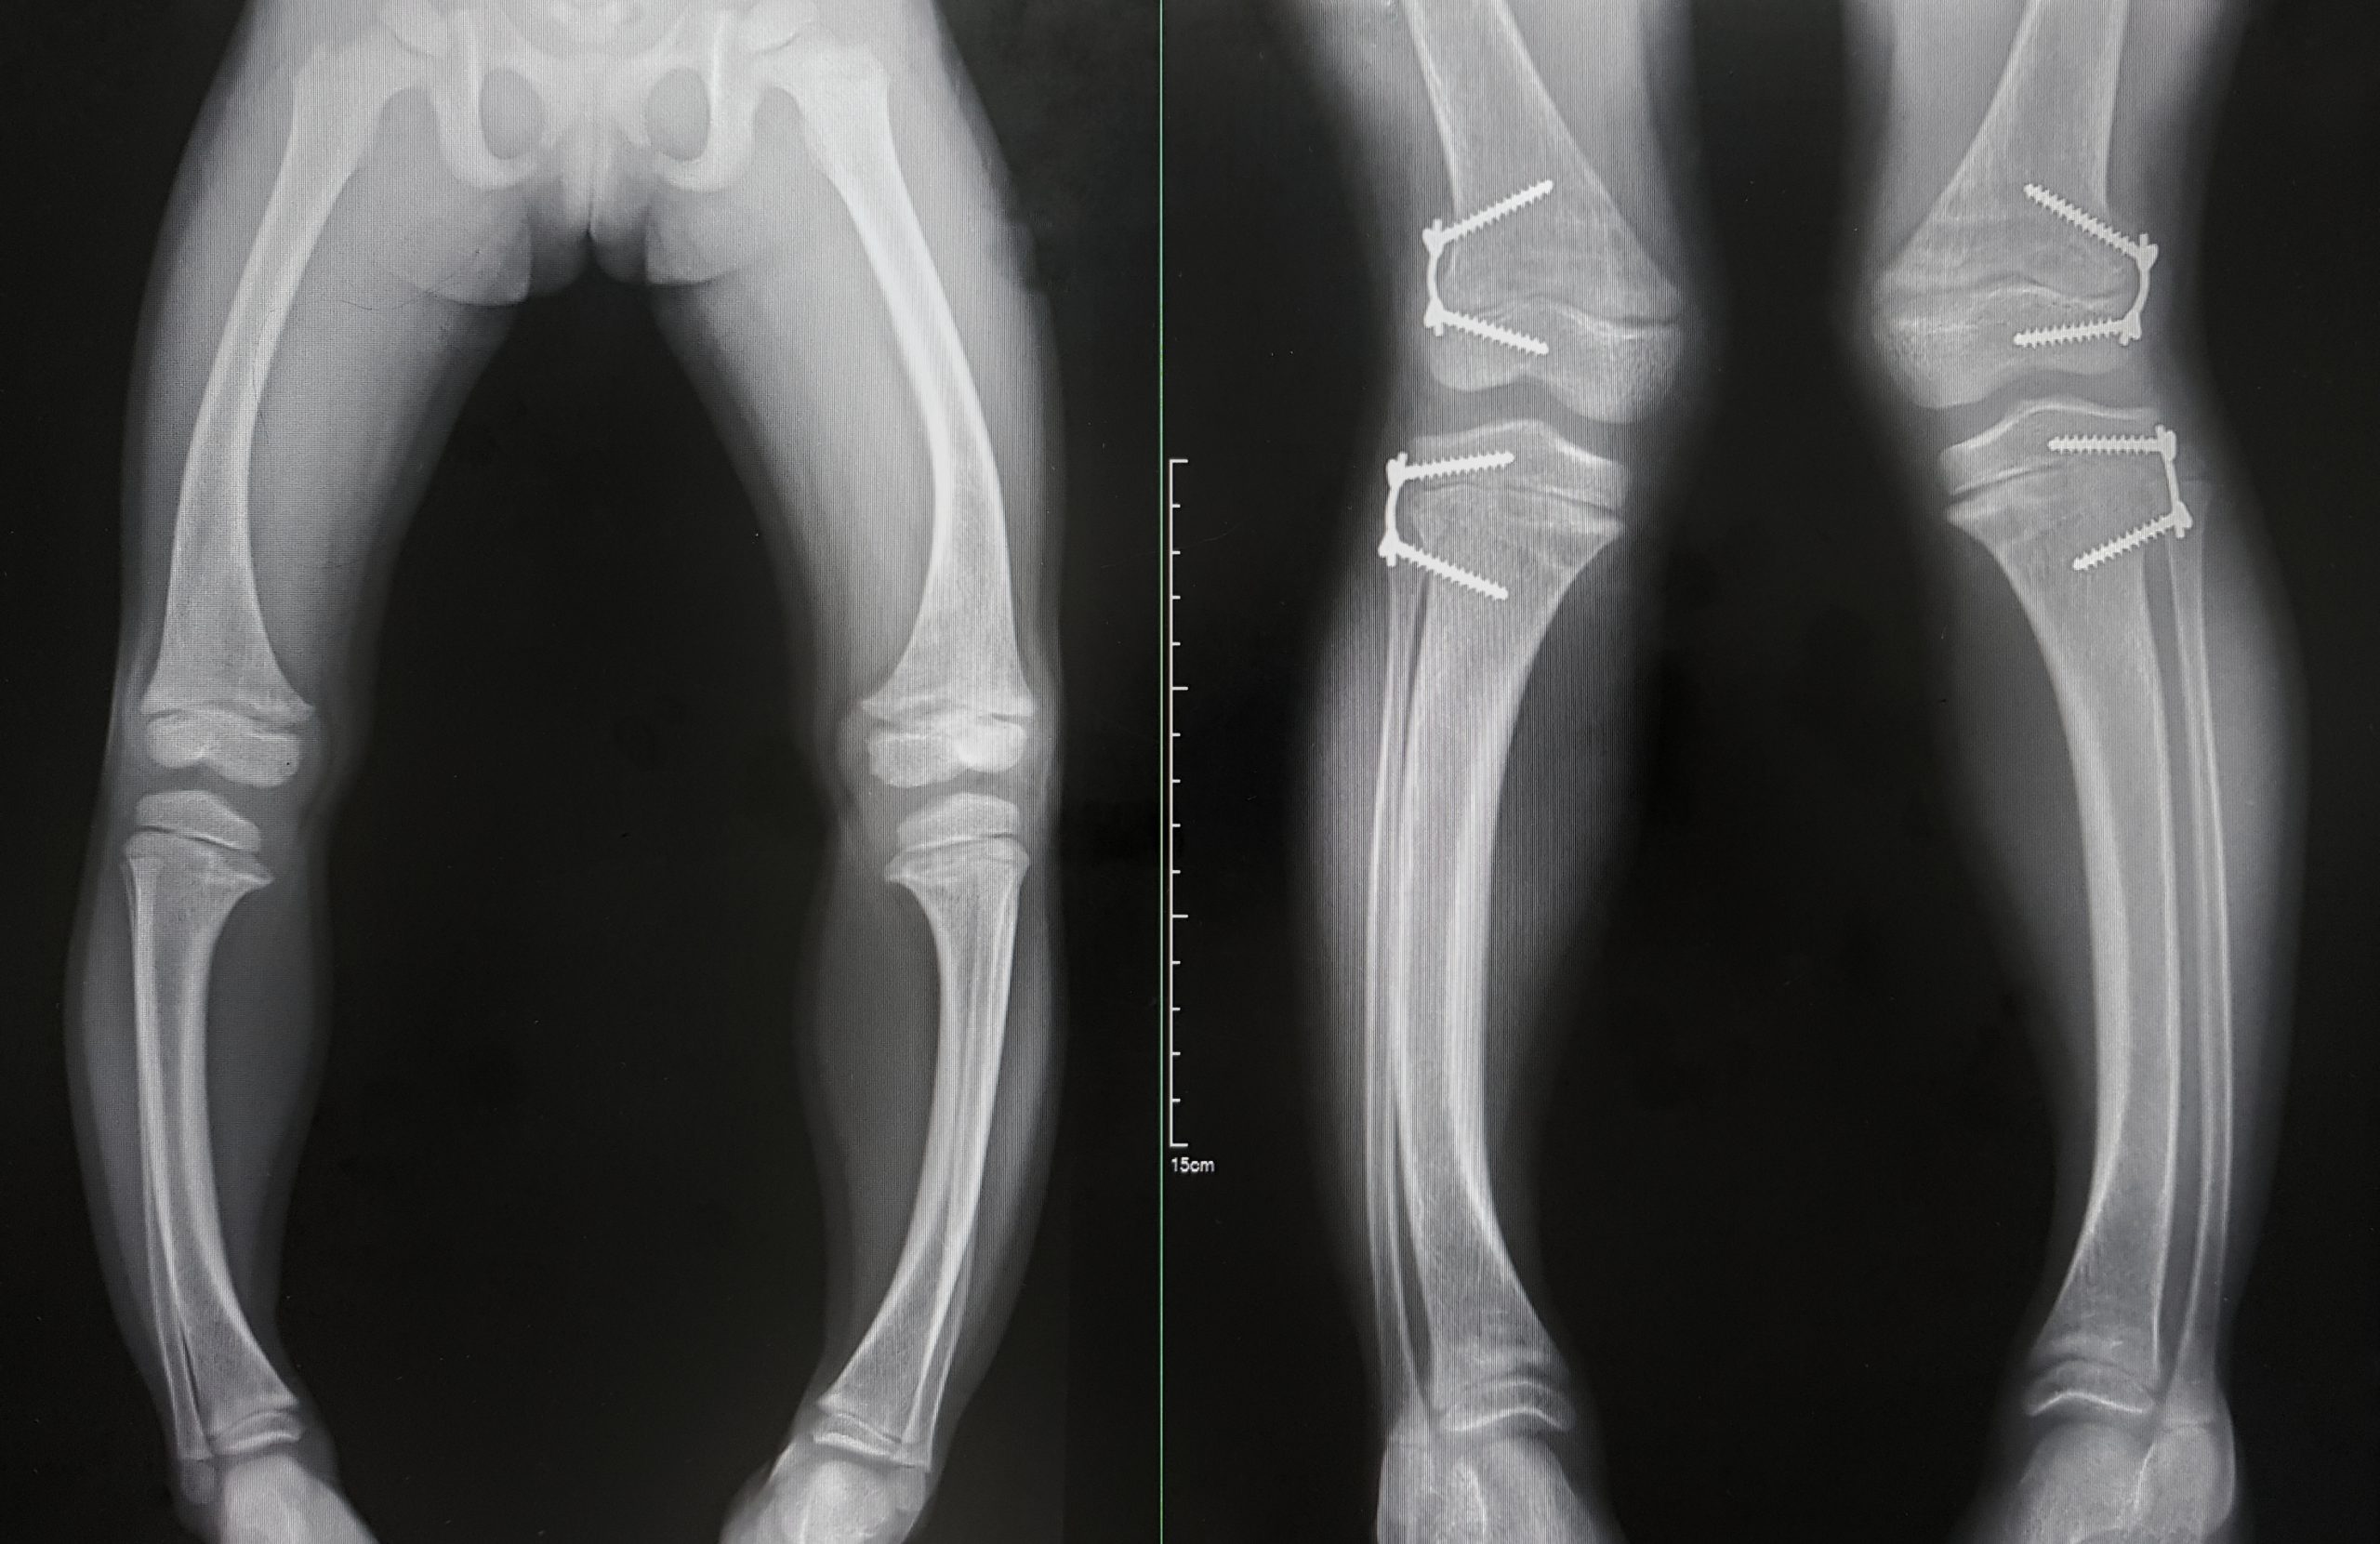

Gibt es in einer Familie bereits XLH-Betroffene, dann werden neu in diese Familie geborene Kinder in der Regel direkt auf die Erkrankung untersucht. Ist das nicht der Fall, werden betroffene Kinder meist klinisch auffällig, wenn sich der Laufbeginn verzögert, da die Knochen nicht stabil genug sind und die Kinder gehemmt sind, sie zu belasten. Sobald sie dann doch beginnen zu laufen, verformen sich durch die fehlende Aushärtung der wachsenden Knochen die Beine. In den meisten Fällen entwickeln sie ausgeprägte O-Beine, aber auch X-Beinstellungen treten auf. Durch die Störung im Knochenstoffwechsel ist zudem häufig auch das Wachstum verzögert. Außerdem härtet häufig der Zahnschmelz nicht richtig aus, was zu Zahnproblemen bis hin zu schmerzhaften Zahnabszessen führen kann. Im Moment gehen wir davon aus, dass bei 70% der Fälle bereits andere Familienmitglieder betroffen sind. 30% werden als spontane Varianten angesehen.

Ist die Diagnose gestellt, gibt es mittlerweile sehr gute Behandlungsmöglichkeiten. Früher war die einzige Möglichkeit die Gabe von Phosphat und aktivem Vitamin D. Das nicht sehr schmackhafte Phosphatpräparat musste mehrmals am Tag oral eingenommen werden, was für betroffene Kinder und ihre Eltern einen Kraftakt darstellte. Glücklicherweise gibt es seit einigen Jahren einen Antikörper, der an der Ursache der Erkrankung ansetzt und bereits in der frühen Kindheit eingesetzt werden kann. Dieser muss nur noch alle zwei Wochen per Injektion verabreicht werden. Diese Antikörpertherapie bringt den Phosphatstoffwechsel wieder ins Gleichgewicht und hat einen deutlichen Benefit für betroffene Kinder: Die Beine wachsen gerade, die Beweglichkeit und körperliche Leistungsfähigkeit ist wesentlich besser, und somit sind die Kinder auch sozial sehr viel besser integriert. Sie können Fangen spielen, mit anderen Kindern herumhüpfen, Sport treiben. Das ist ein ganz wichtiger Punkt, da die Lebensqualität Betroffener so stark verbessert werden kann.